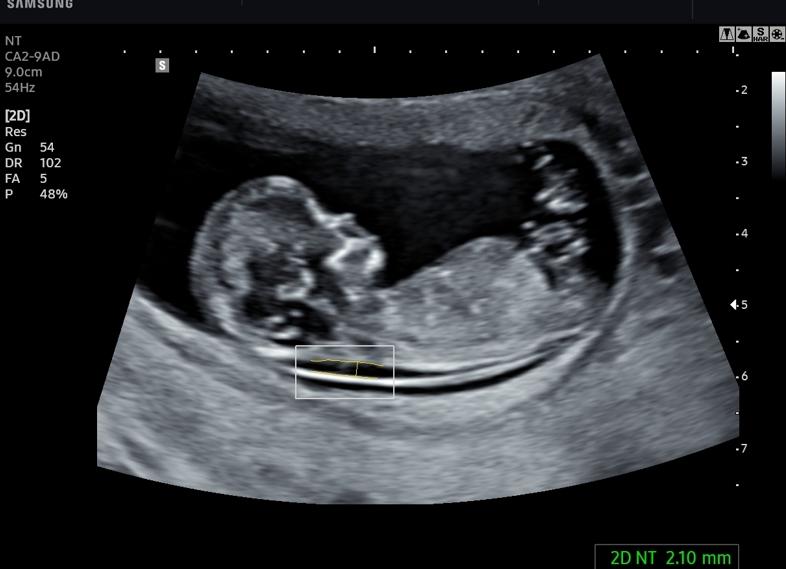

При проведении скрининг УЗИ в 12 недель беременности особое внимание уделяется головному мозгу, который к данному сроку должен иметь два полушария. Кроме того процедура позволяет врачу проанализировать воротниковую область и установить ее толщину, которая показывает, есть ли риск возникновения болезни Дауна. Если показатели толщины не соответствуют норме (в пределах от 2 до 3 мм), а превышают ее, то врач будет подозревать у плода наличие хромосомных аномалий. В этом случае усиливается контроль над состоянием будущей мамы и тем, как развивается ребенок, и повторно делается скрининг УЗИ через 2 недели.

Есть несколько показателей, которые исследует врач. Самый важный — ТВП. Толщина воротничкового пространства, это толщина мягких тканей вокруг шеи. В норме считается показатель не более 3 мм. Если показатель повышен, это может свидетельствовать о возможных патологиях.

Для определения отклонений требуется эти две величины. Измерение ТВП имеет смысл при размерах КТР 45–85 мм, поэтому важно проводить скрининг не раньше 11 и не позже 13 недели.

• Воротниковая зона – один из наиболее важных показателей, которые измеряют только на УЗИ в 12 недель. В норме она не превышает 3 мм. Большие размеры могут говорить о такой серьёзной генетической патологии, как синдром Дауна.